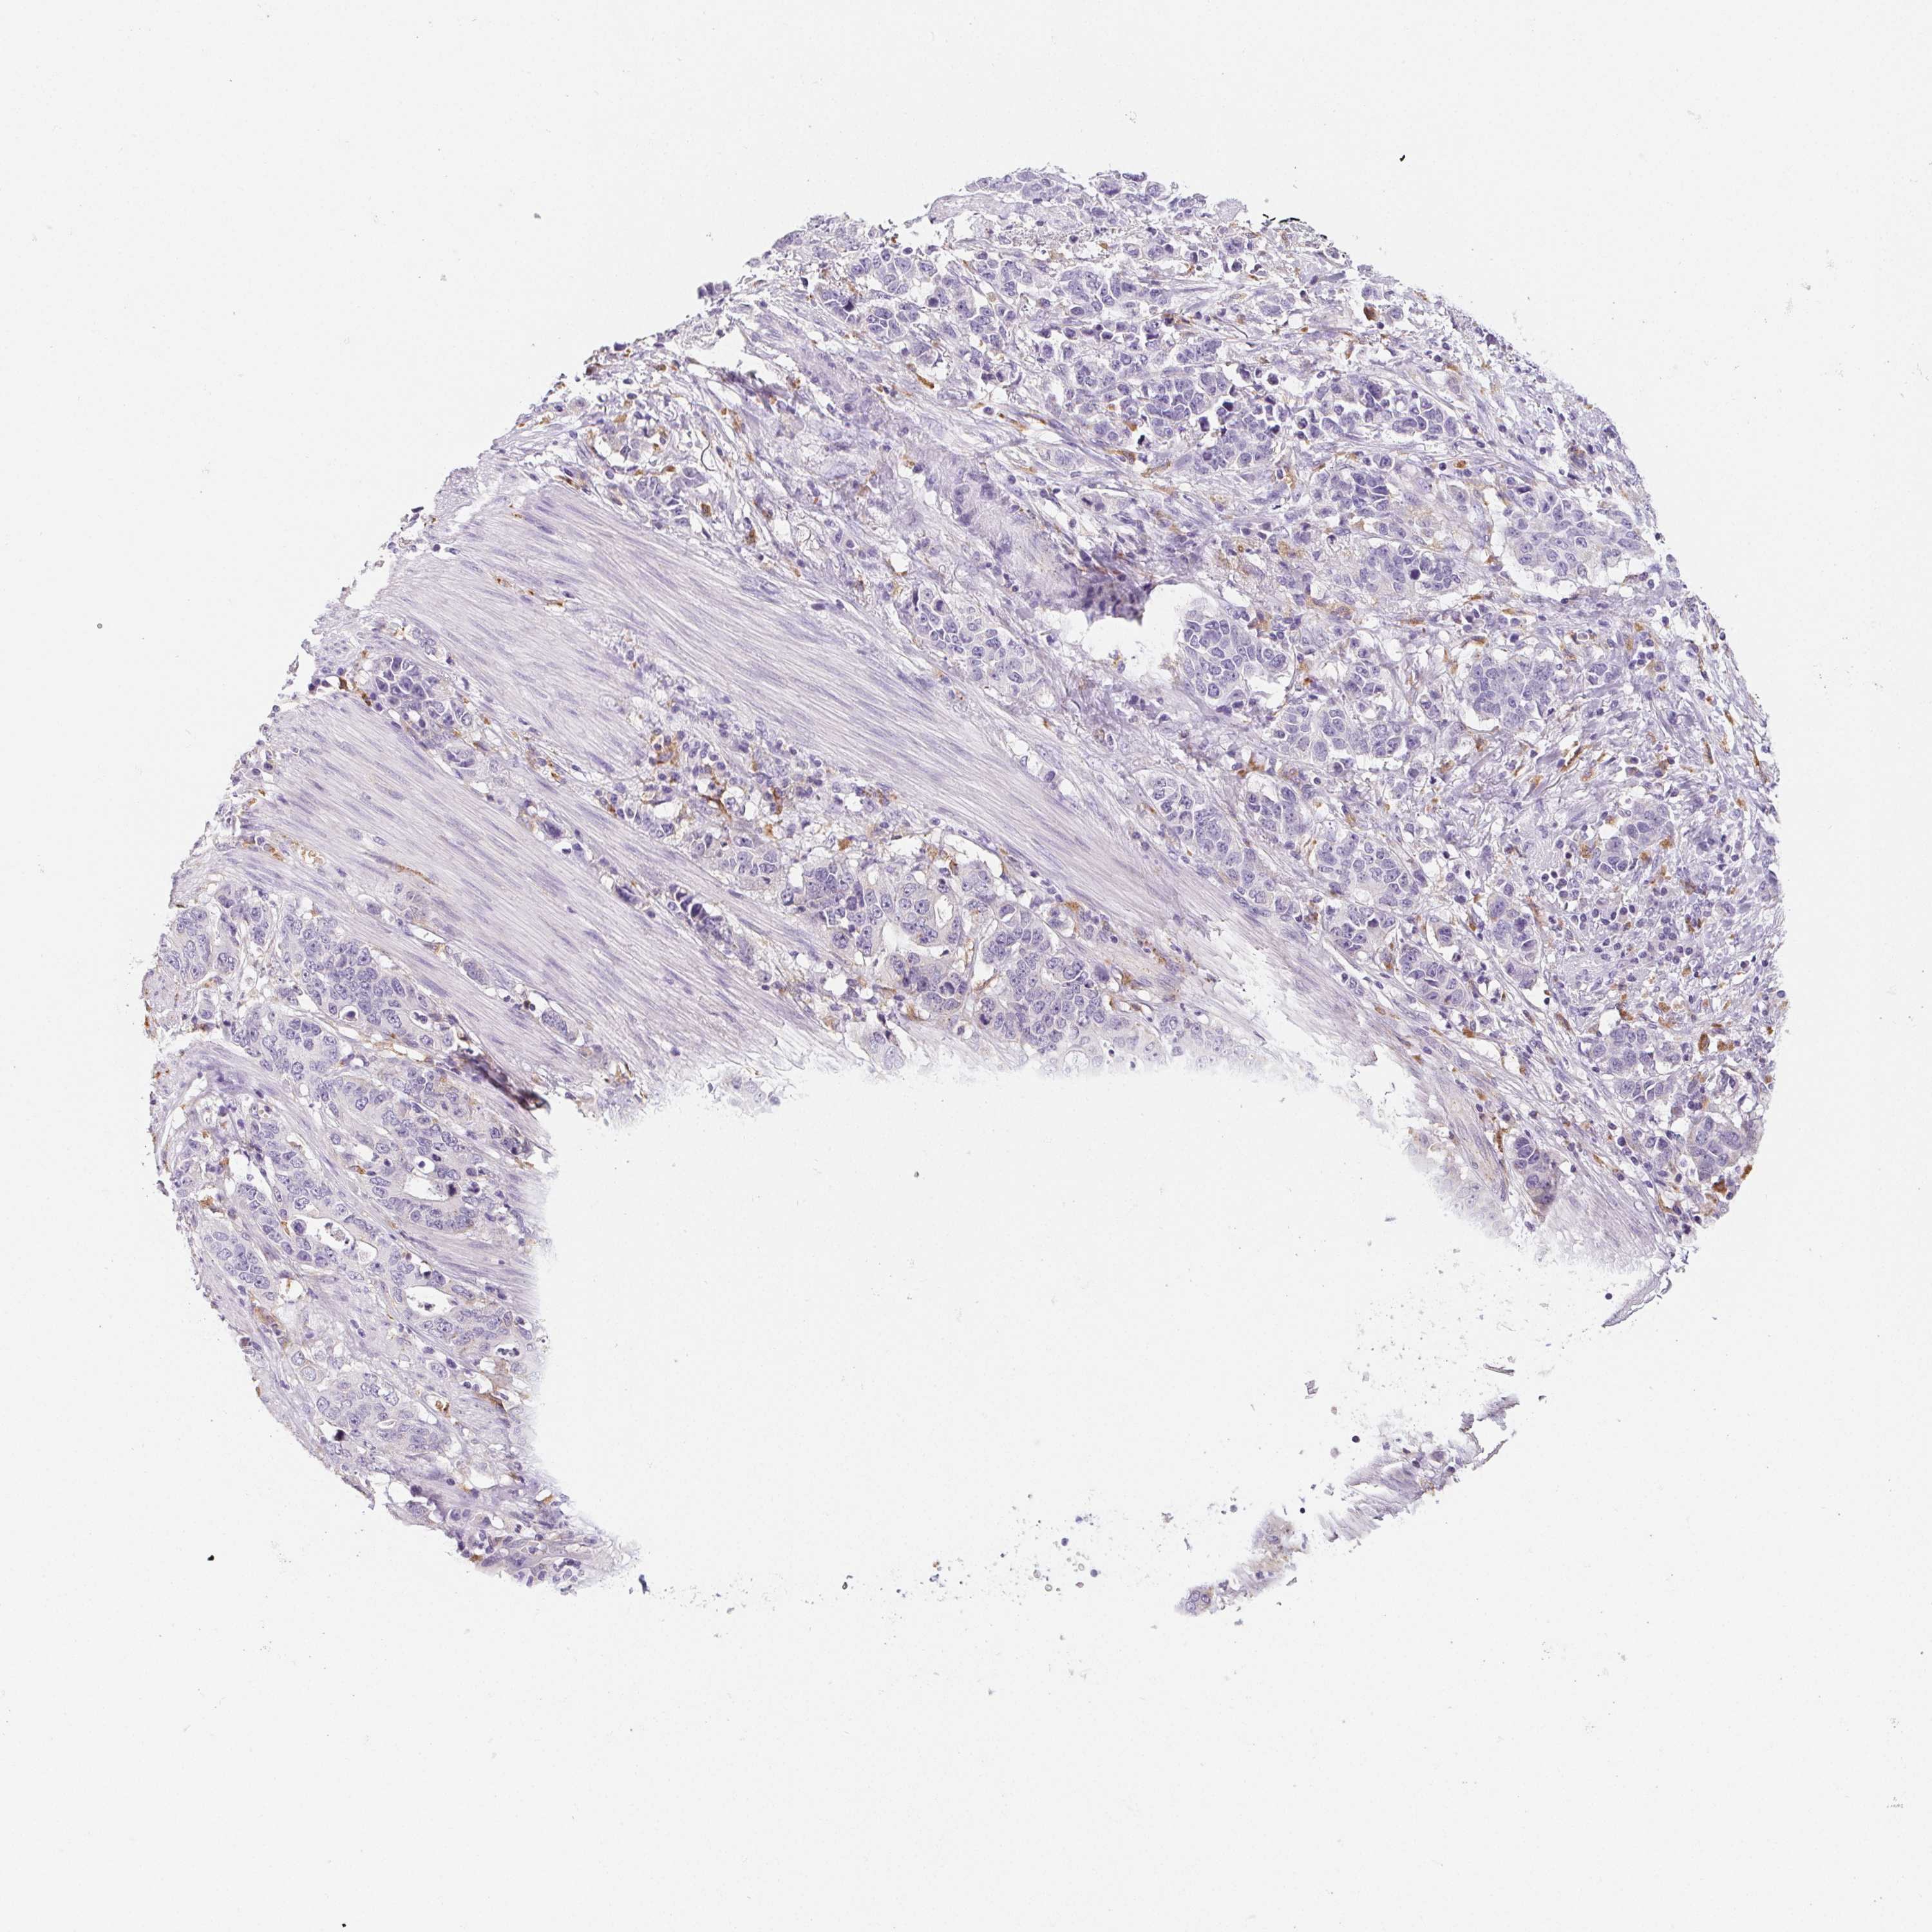

STOMACH CANCER - Protein expressioni

A mouse-over function shows sample information and annotation data. Click on an image to view it in a full screen mode. Samples can be filtered based on level of antibody staining by selecting one or several of the following categories: high, medium, low and not detected. The assay and annotation is described here.

Note that samples used for immunohistochemistry by the Human Protein Atlas do not correspond to samples in the TCGA dataset.

Antibody stainingi

Antibody staining in the annotated cell types in the current human tissue is reported as not detected, low, medium, or high, based on conventional immunohistochemistry profiling in selected tissues. This score is based on the combination of the staining intensity and fraction of stained cells.

Each image is clickable and will lead to virtual microscopy that enables deeper exploration of all samples and also displays staining intensity scores, fraction scores and subcellular localization as well as patient and tissue information for each sample.

Antibody HPA057052

Antibody CAB034892

Staining

High

Medium

Low

Not detected

Intensity

Strong

Moderate

Weak

Negative

Quantity

>75%

75%-25%

<25%

None

Location

Nuclear

Cytoplasmic/membranous

Cytoplasmic/membranous,nuclear

Adenocarcinoma, NOS